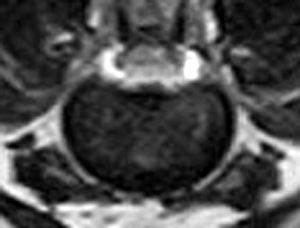

犬の多発性胸腰部椎間板ヘルニアのMRI検査

市外の先生からダックスちゃんの腰の痛みの精査依頼でMRI検査のご紹介がありました。検査結果から多発性胸腰部椎間板ヘルニアを認めました。その後かかりつけの先生のもとで内科治療となりました。